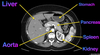

label the arrows on this abdominal CT

label this CT

Label the: * liver * gall bladder * ascending colon * bladder

label the: * Kidney * Aorta * Stomach * Liver * IVC * Aorta